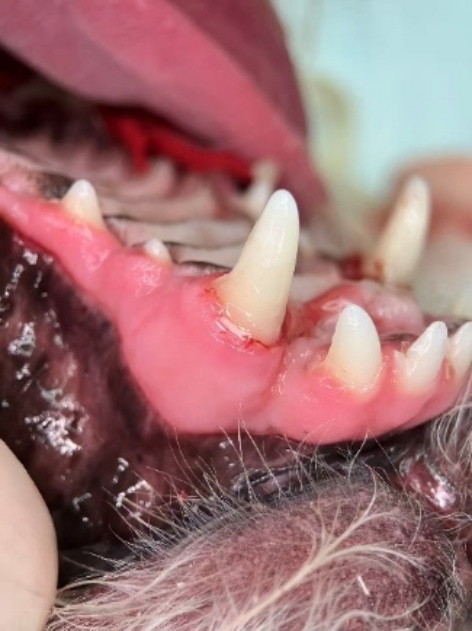

Figure 2. Postoperative appearance after reduction and fixation in the affected dog

2. 患犬复位固定术后外观

随后采用0.5 mm不锈钢丝进行“8”字形环扎:钢丝依次穿绕复位牙与上颌对侧犬齿,通过加力旋紧形成初步固位。再于钢丝外层包覆3M冠桥复合树脂(ESPE Protemp),自固化后形成连续夹板,与对侧犬齿形成稳固支撑(图2)。树脂厚度约2 mm,以保证结构强度同时避免影响咬合。术中注意保留牙龈边缘,防止压迫软组织。